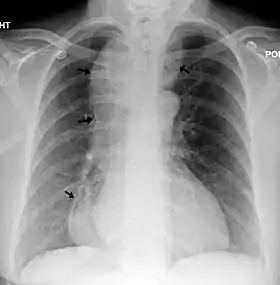

Radiographie thoracique d'un individu atteint d'achalasie. Les flèches indiquent les zones de dilatation œsophagienne extrême. | ||